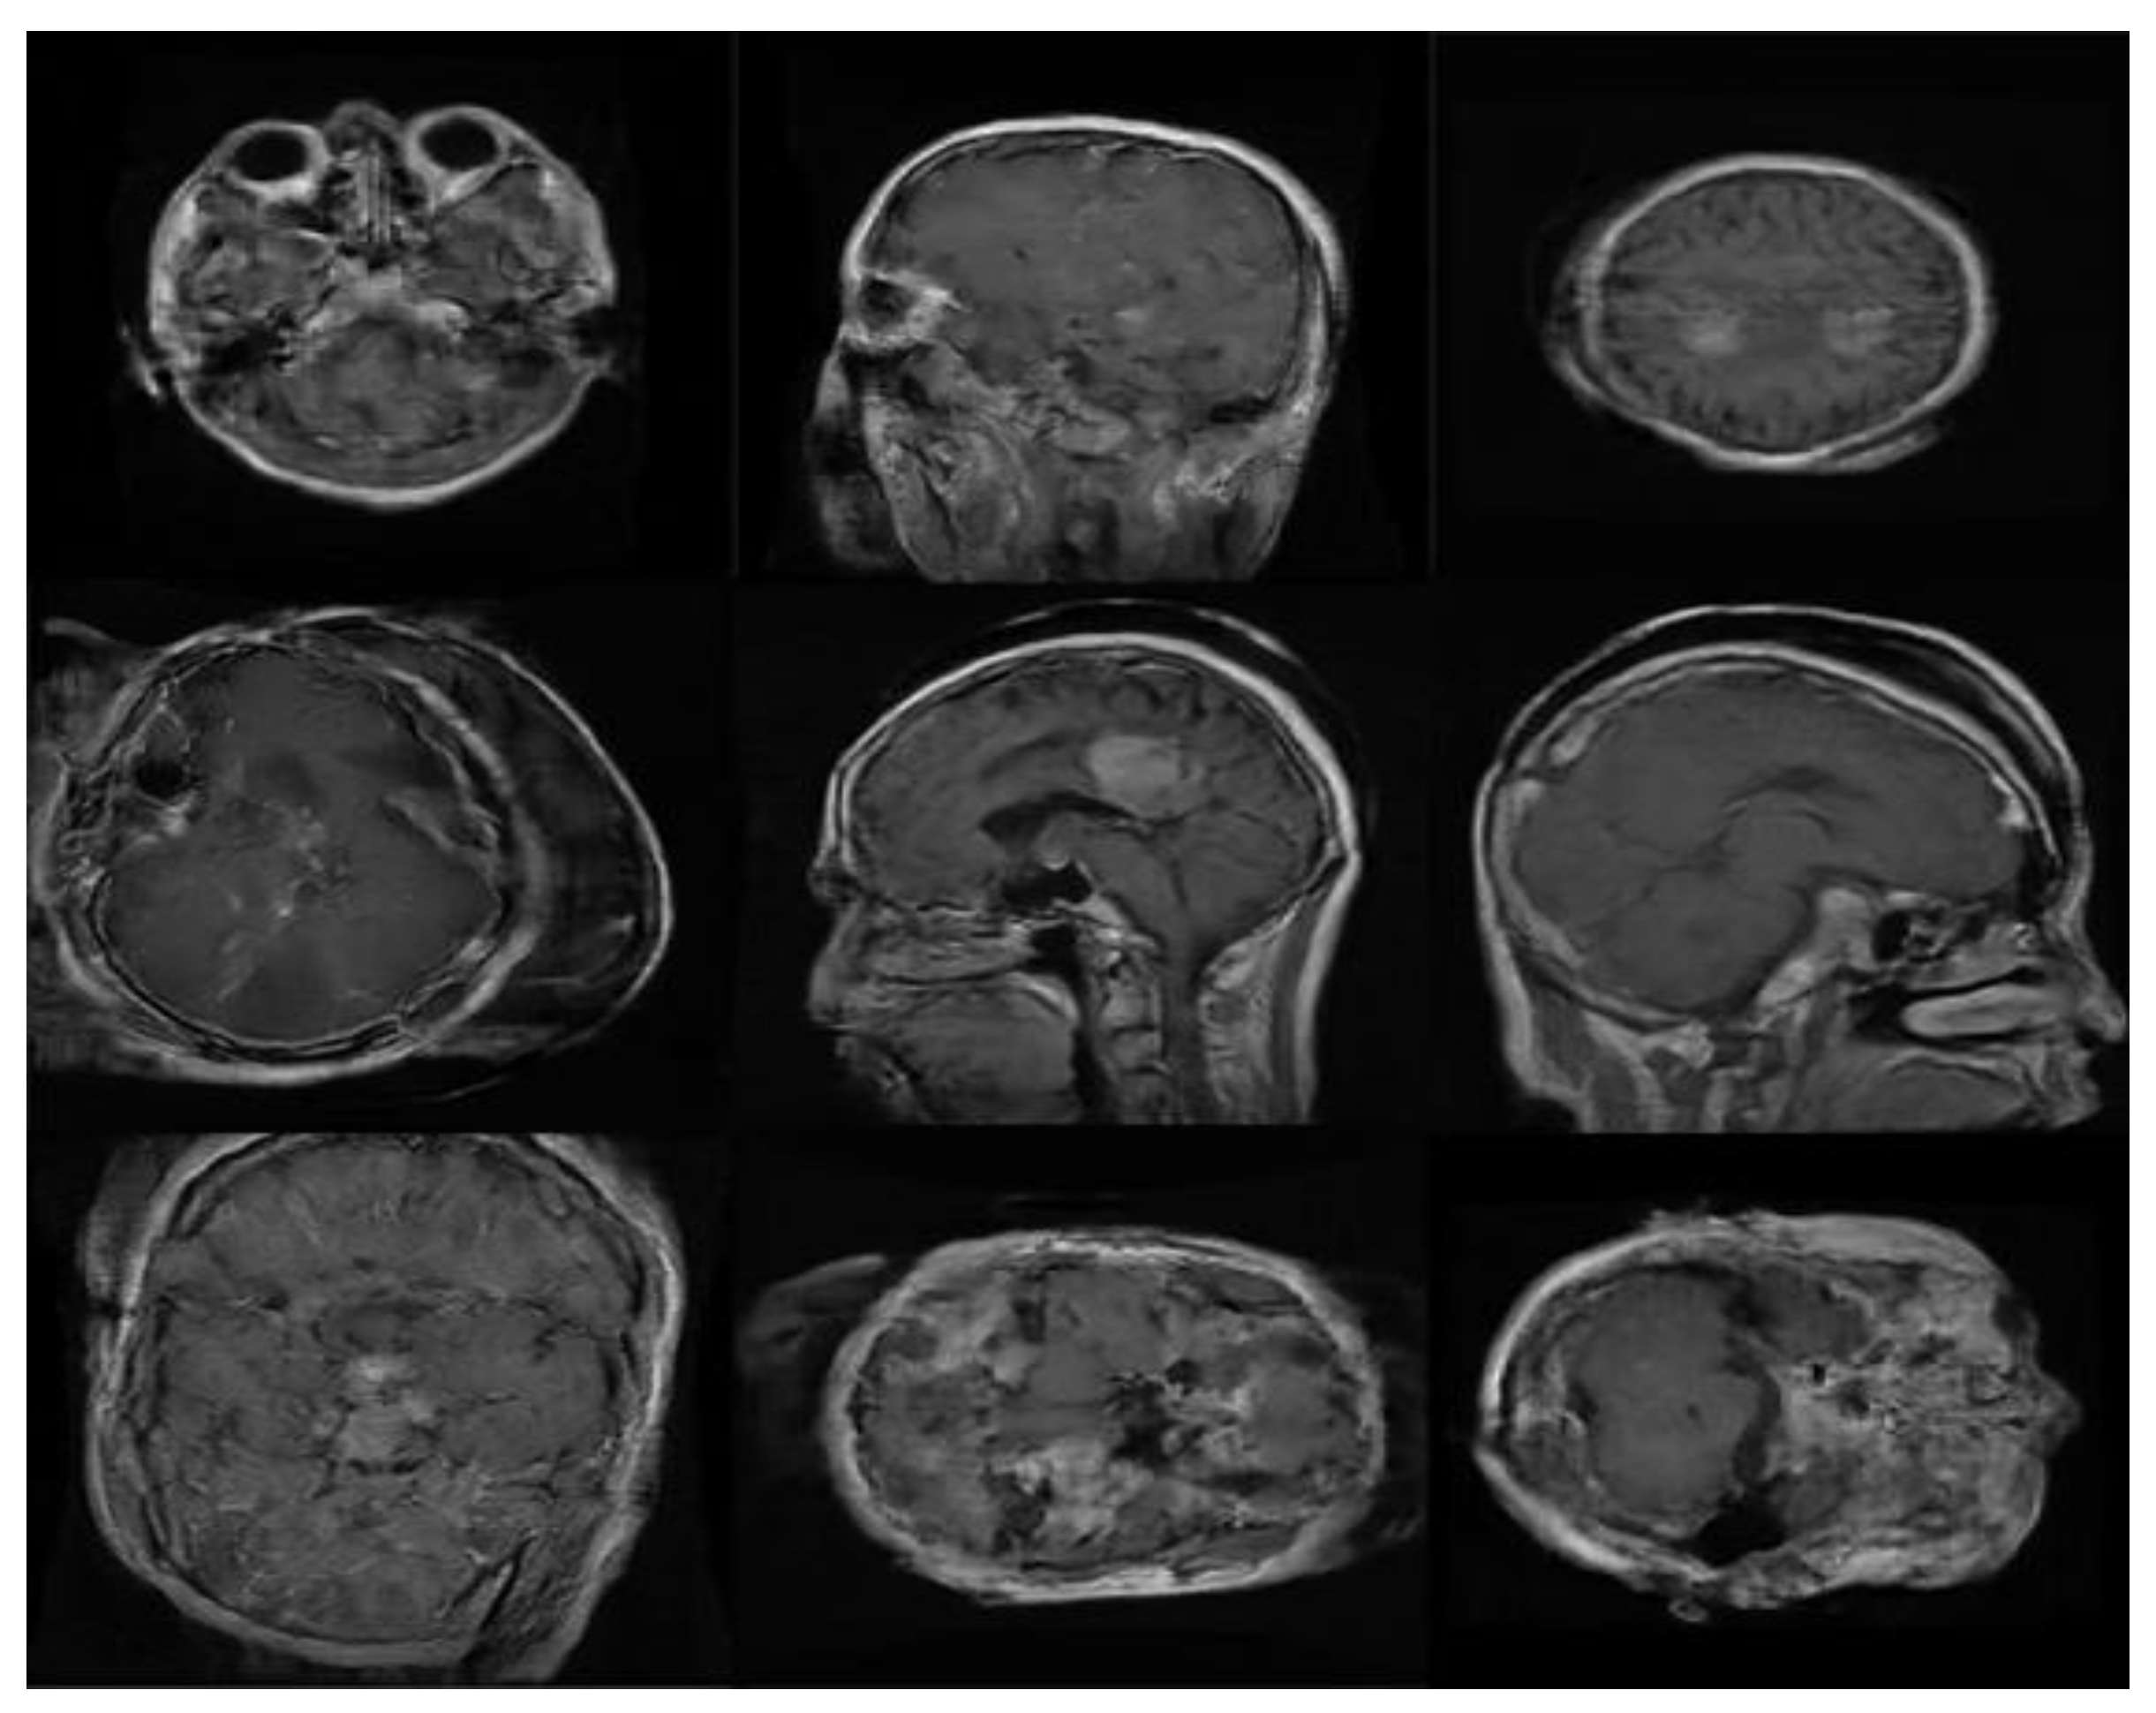

2.1. Data set for the Study

2.2.2. PGGAN-Based Data Augmentation